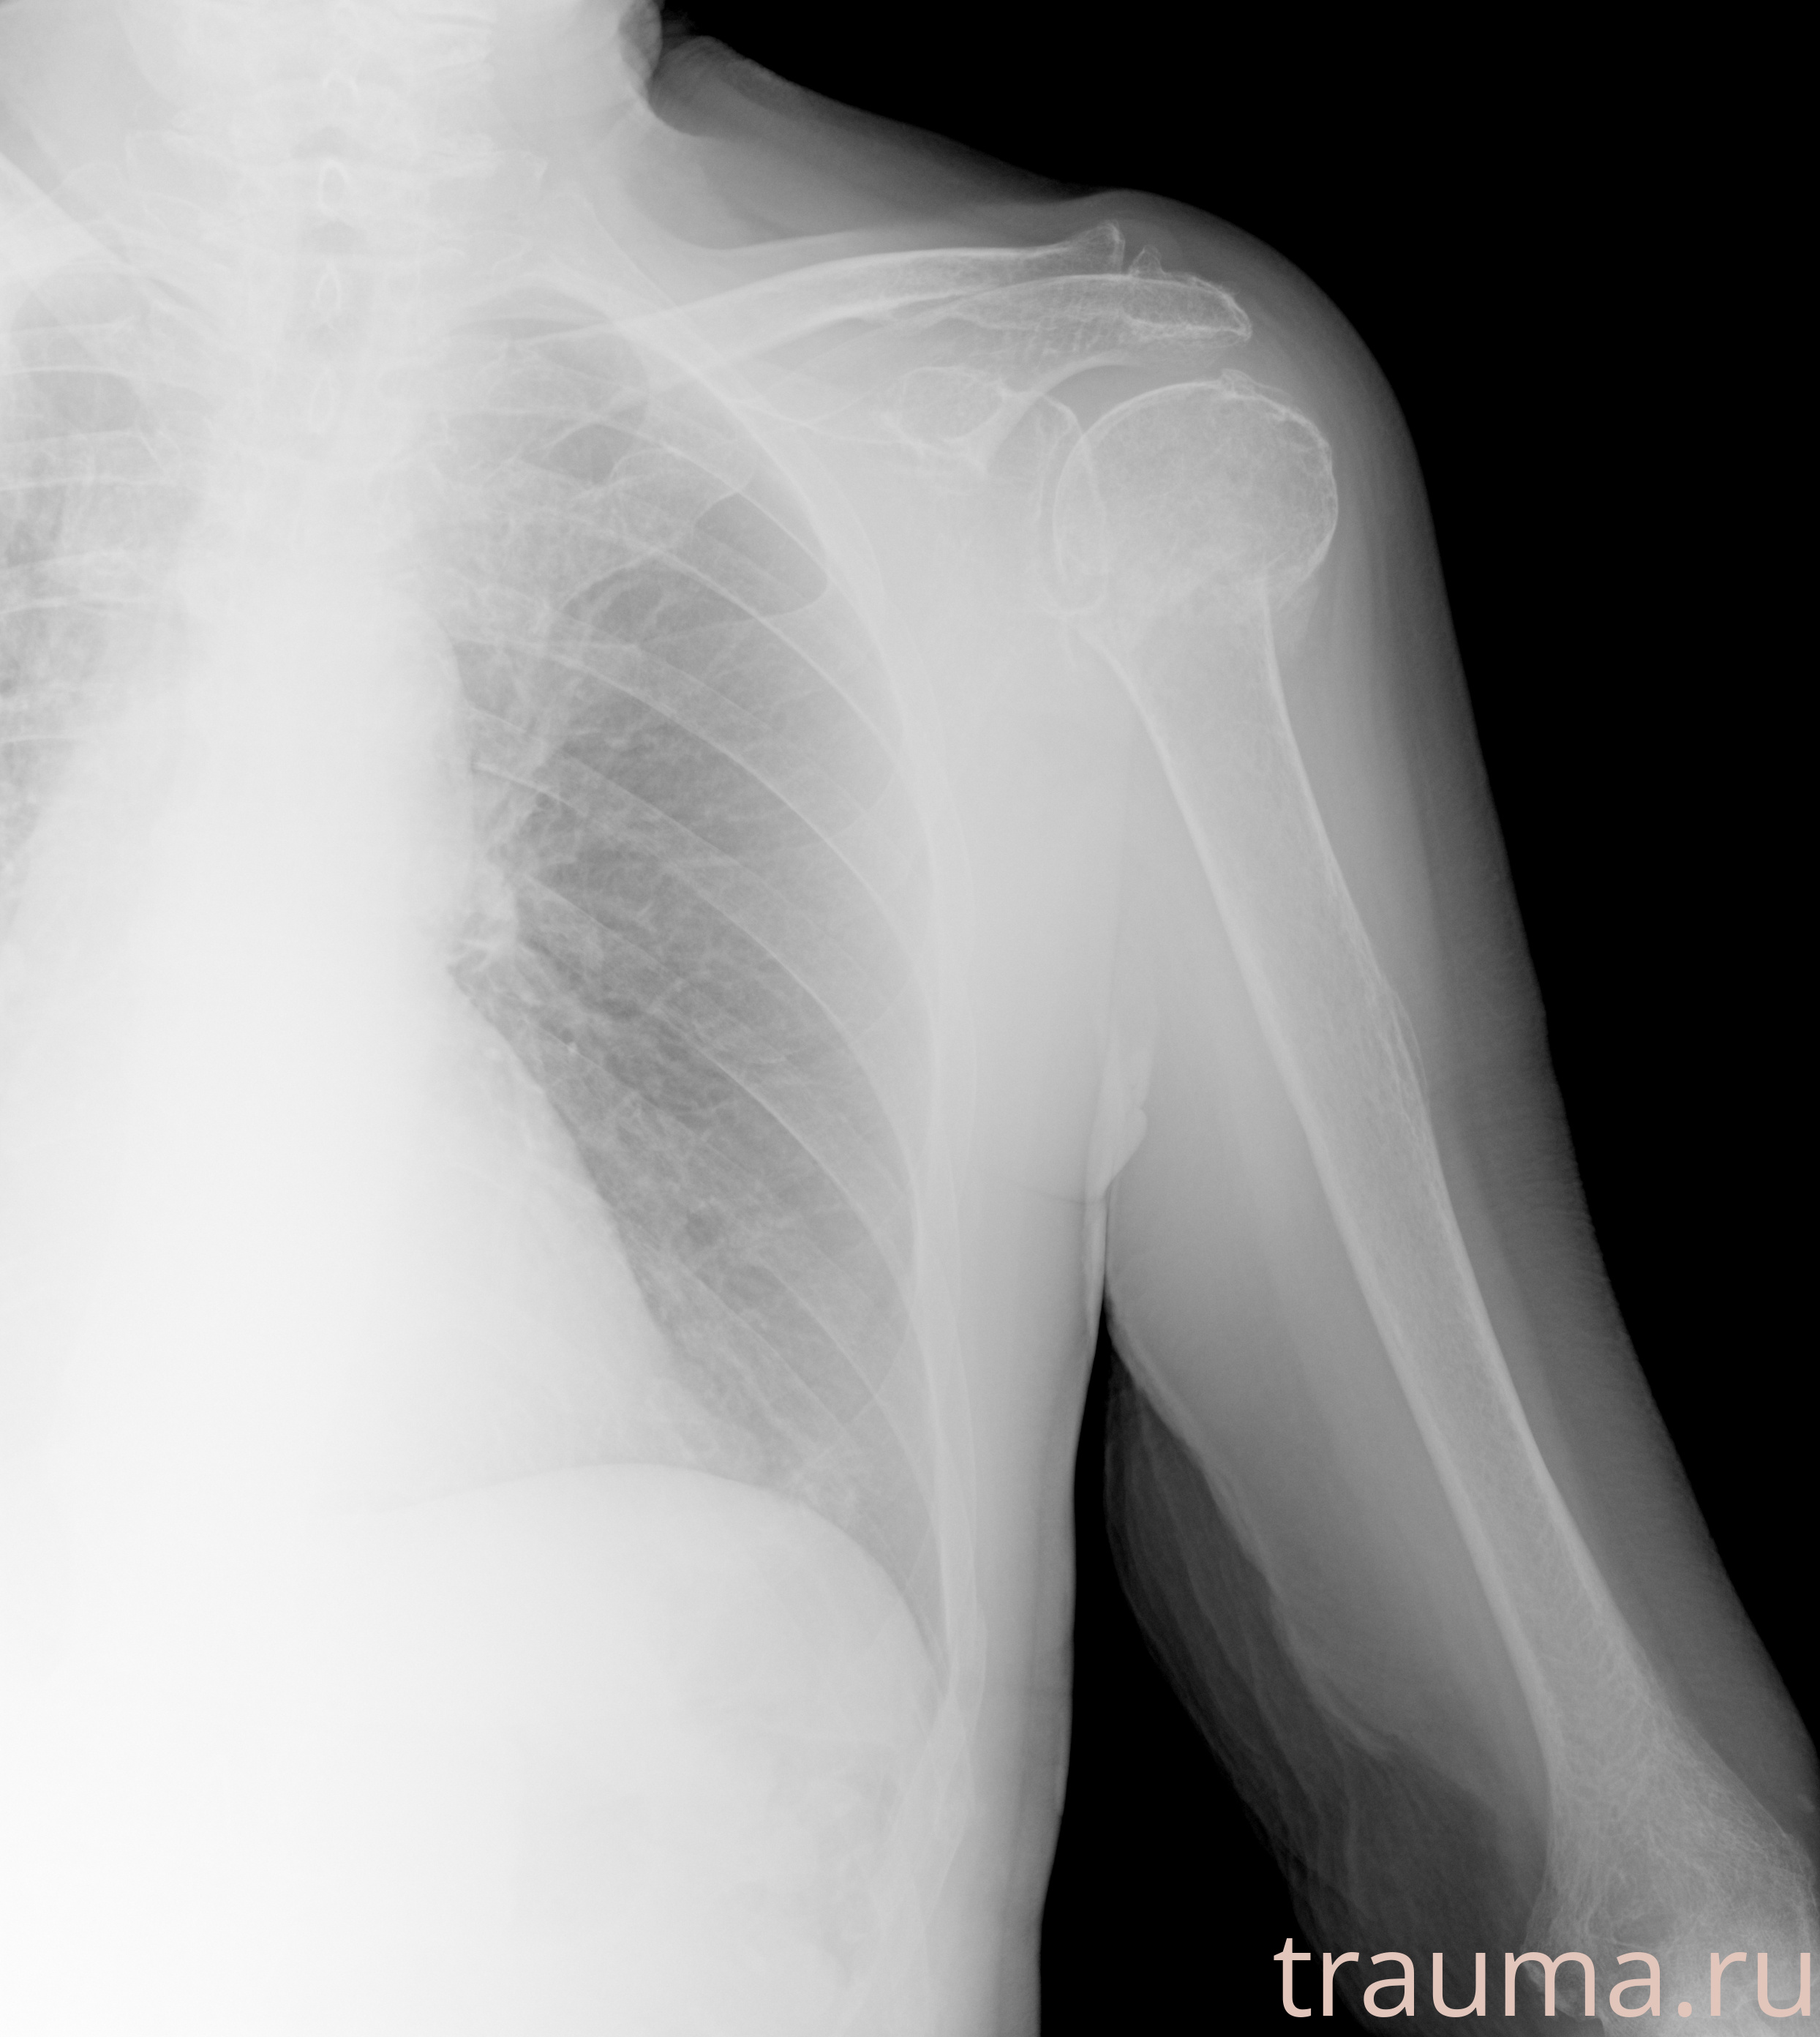

Рентгенограммы

Рентген на дому: по вашему адресу приезжает врач-рентгенолог, травматолог-ортопед с мобильным рентгеновским аппаратом, проводит диагностику травмы или заболевания, делает необходимые рентгенограммы, дает рекомендации по дальнейшему лечению. Получить качественные снимки в домашних условиях возможно благодаря уникальной методике, разработанной МосРентген Центром для института  Склифосовского